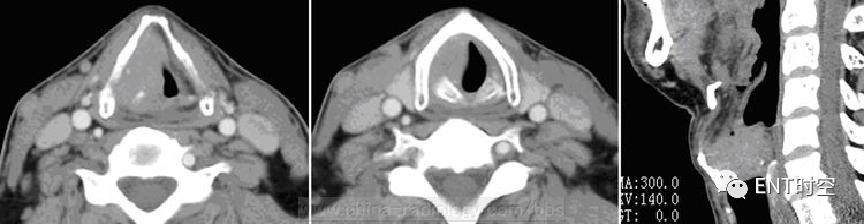

男性,67岁,咽部异物感半年,咽部阻塞感、声嘶伴呼吸不畅半月,痰中带血4天

(一)CT扫描:示右侧梨状隐窝区可见软组织密度影,病变边界清楚,形态尚规则,平扫呈等密度、增强扫描病变明显强化。病变部分沿喉咽后壁蔓延。骨质未见明显破坏。(二)诊断:(右下咽)中-低分化鳞状细胞癌。(病理确诊) (三)鉴别诊断:1.咽旁脓肿。 2.喉癌 。

(四)CT表现:1.病变密度;平扫呈等或稍低密度,增强扫描病变有明显不均匀强化。2.梨状窝变窄或消失;主要表现在梨状窝前壁、侧壁或后壁明显增厚,杓会厌皱襞增厚,致梨状窝狭窄或消失。3.咽后软组织增厚;咽后壁癌或环后癌主要表现在咽后壁或环后区增厚,杓-椎距或环-椎距明显增宽。4.喉及邻近结构受累;肿瘤向周围侵犯,首先累及喉旁结构,声带受侵、增厚,喉旁间隙增宽、软组织肿块。5.喉软骨破坏。6.颈部淋巴结转移。7.食管及其他结构受累。